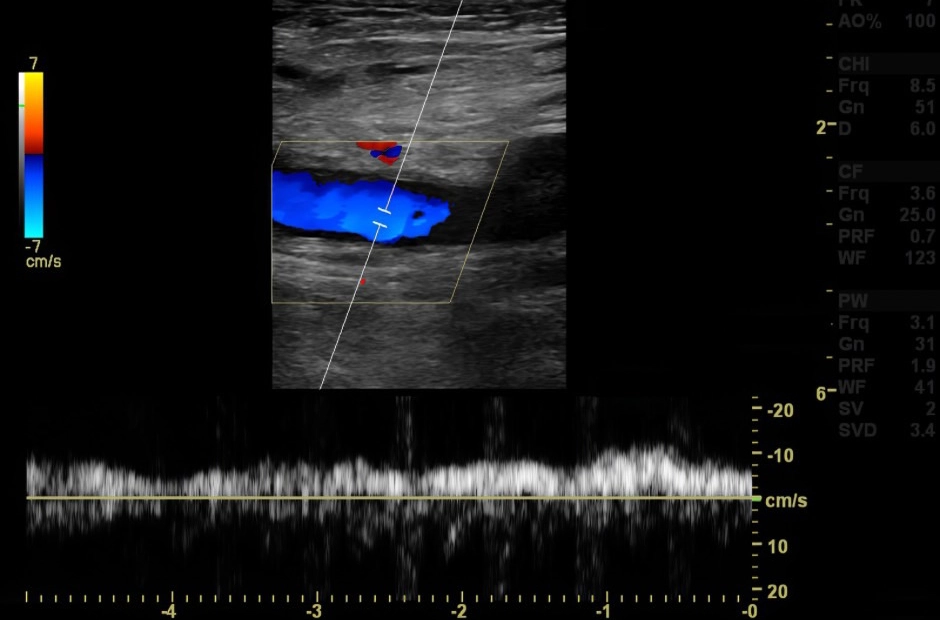

การวินิจฉัย

ทำได้โดยการตรวจอัลตราซาวด์หลอดเลือดที่ขา (Duplex Ultrasound) ซึ่งเป็นการตรวจที่มีความจำเพาะ และมีความแม่นยำสูงในการตรวจหาความผิดปกติของหลอดเลือด อีกทั้งยังมีส่วนช่วยในการวางแผนการรักษาให้เหมาะสมกับผู้ป่วยแต่ละราย